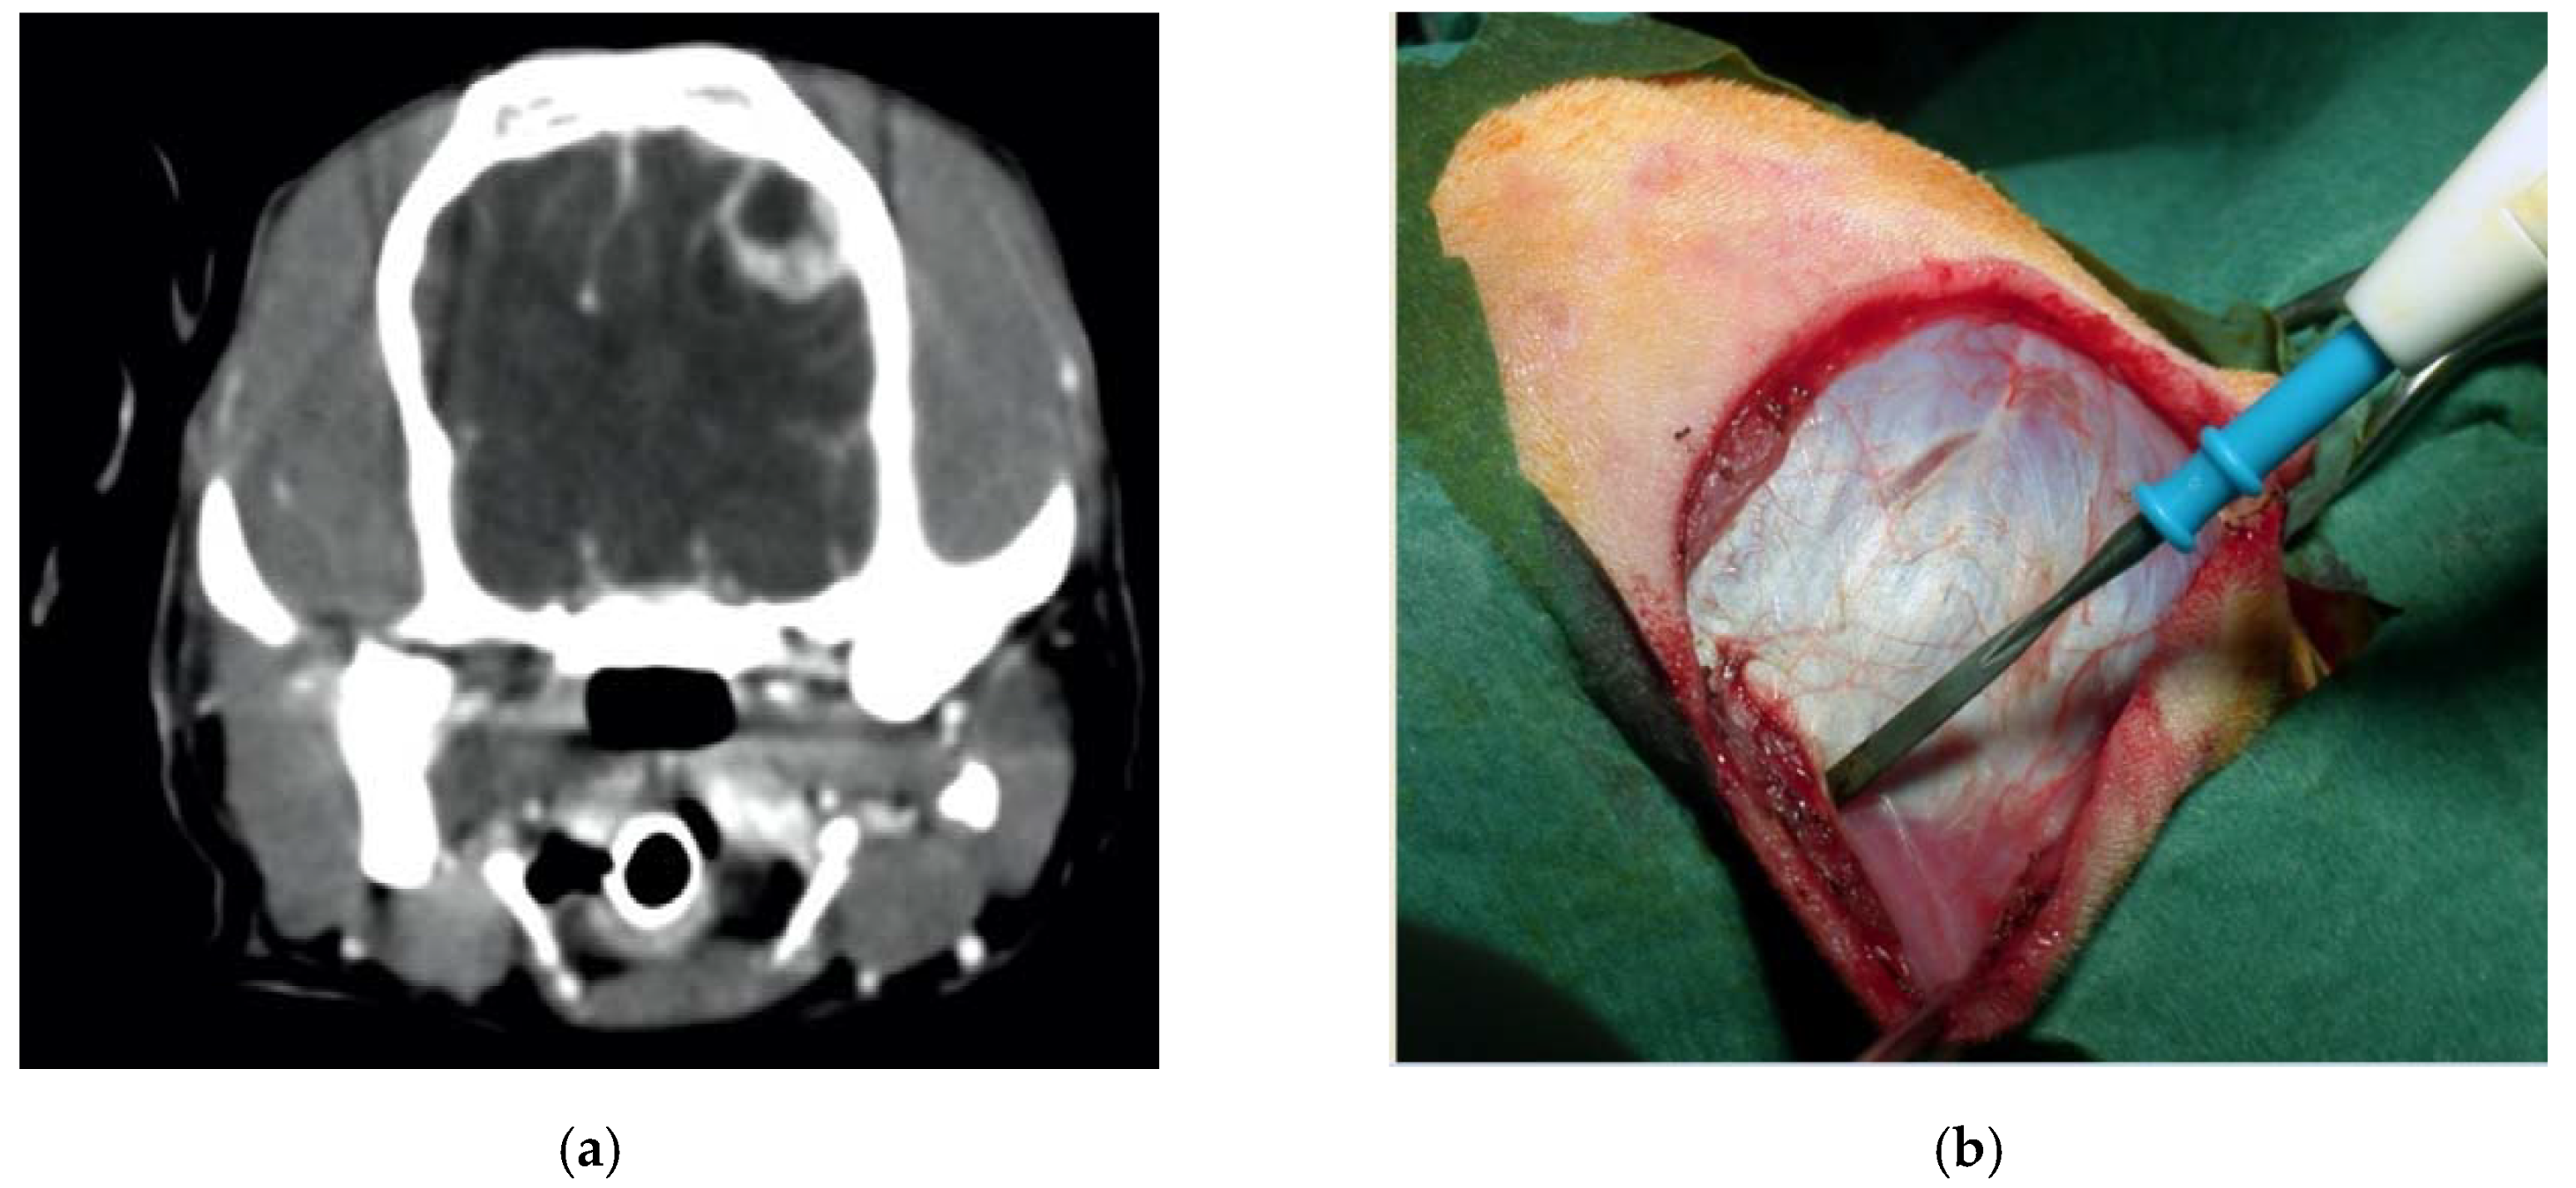

Cat, male, three years old, 3 kg. Firearm trauma with a secondary spinal cord compression due to a retained lead shot. The cat was paraplegic. He underwent to a laminectomy and spinal cord decompression by means of the piezoelectric bone scalpel, where, once again, it was possible to spare completely the spinal cord (Figure 8). Recovery was very fast, without complications.

Figure 8.

X-ray in latero-lateral (a) and ventro-dorsal (b) projection, showing multiple retained lead shots in a cat paraplegic because victim of a firearm trauma. One of the intrathecal lead shots caused a spinal cord contusion and partial compression. A subdural hematoma was also present. Intraoperative pictures showing lumbar spinal cord after decompressive one-level laminectomy performed with piezoelectric scalpel and an angled small saw tip (OT7S-3, Osteotomy Tips Kit, Mectron Medical Technology, Genoa, Italy) (c,d). Six-months postoperative ventro-dorsal X-ray showing the site of the laminectomy (e).